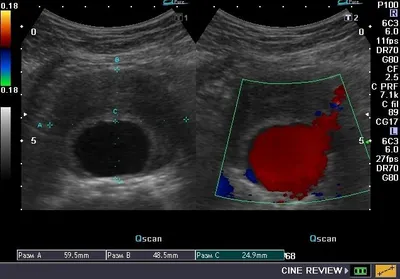

Случаи из практики судового врача (хирурга).. Случай паранефрального мочевого затёка (уриномы) вследствие ушиба (разрыва) ЧЛС почки... Разрешился без разреза, моча эвакуировалась пункциями... длител

4 мар. 2026 г.

620 6 2